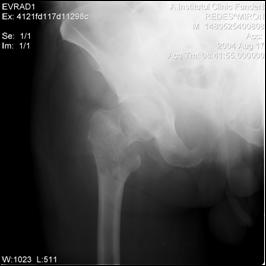

Figura 42. Metastaza in articulatia coxo-femurala dreapta.

Figura 44. Metastaza in articulatia coxo-femurala